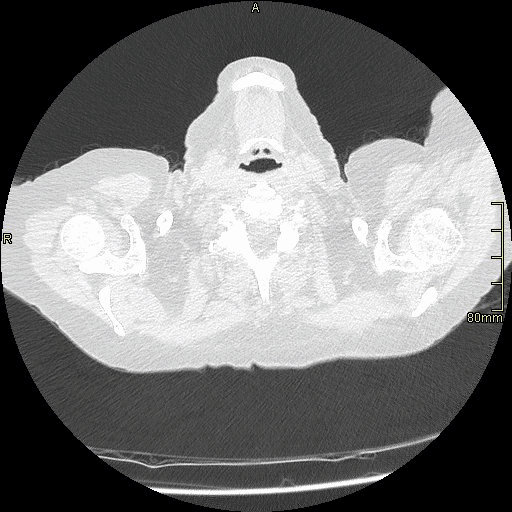

HRCT - Axial Prone Inspiration (Soft Tissue Window)

HRCT - Axial Supine Inspiration (Soft Tissue Window)

HRCT - Axial Supine Expiration (Soft Tissue Window)